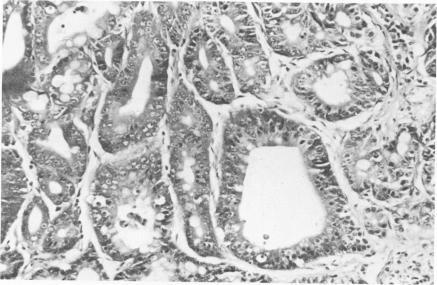

Animal model: carcinoids and adenocarcinoma of the glandular stomach of Praomys (Mastomys) natalensis.

Am J Pathol. 1979 Jul;96(1):359-62.

PMID:464025

原文链接:https://pmc.ncbi.nlm.nih.gov/articles/PMC2042366/